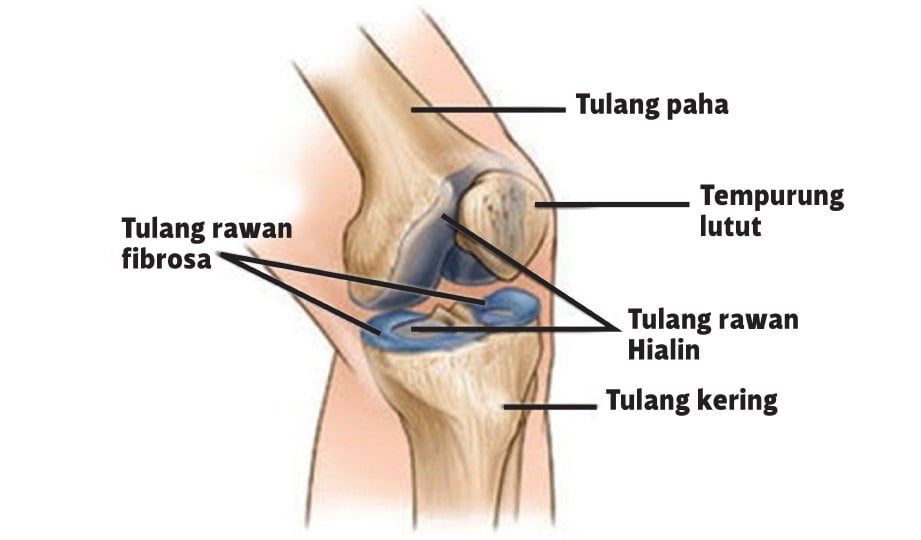

Bebas sakit sendi lutut | Harian Metro

Bebas sakit sendi lutut | Harian Metro

Bebas sakit sendi lutut | Harian Metro

Bebas sakit sendi lutut | Harian Metro

Bebas sakit sendi lutut | Harian Metro

Bebas sakit sendi lutut | Harian Metro